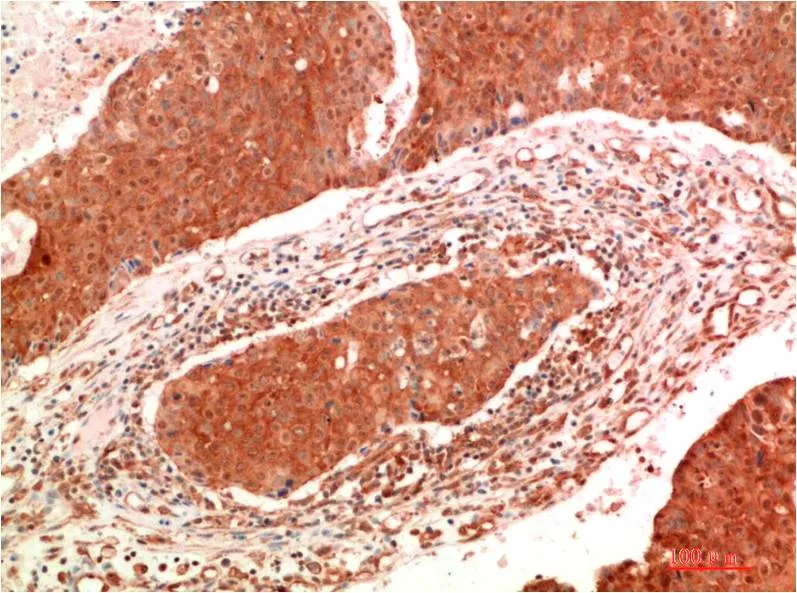

JAK2 (6B4) Mouse Monoclonal Antibody

Cat: AMM00767

Application:IHC-P

Reactivity:Human,Rat,Mouse

Conjugate:Unconjugated

Gene Name:JAK2